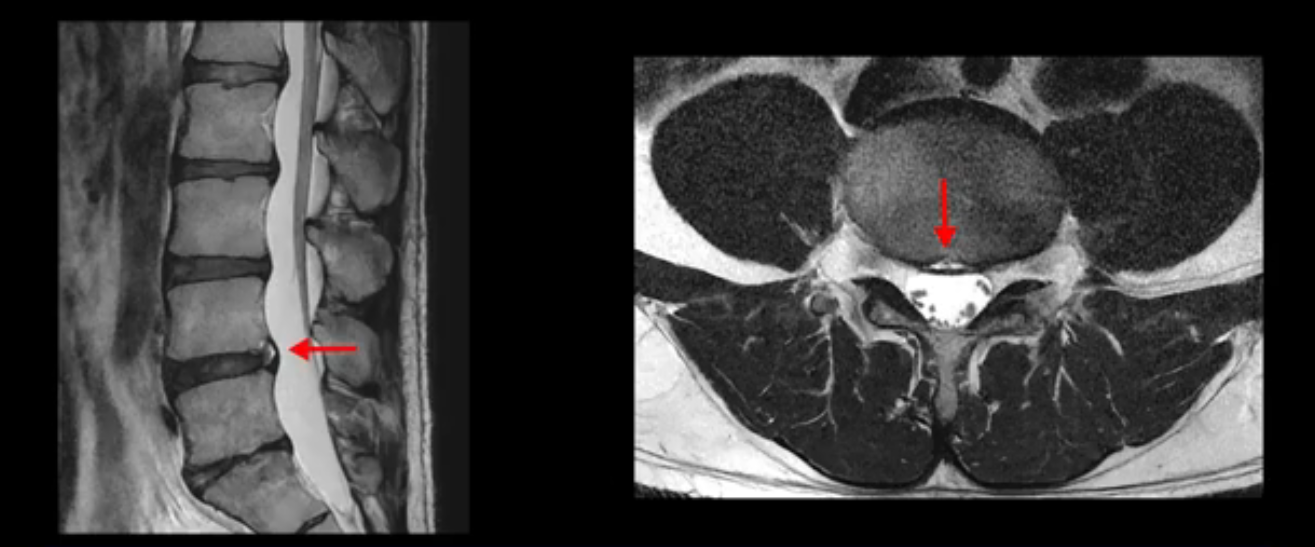

4번 5번은 가운데로 섬유륜이 찢어져서 디스크가 살짝 밀려나와 있지만 역시나 최근에 찢어지고 밀려나온 걸로 판단되지 않고 오래 전에 찢어진 흔적으로 보입니다.

왜 최근에 찢어진 급성이 아니고 오래된 거라고 하는지 이 부분도 뒤에 한꺼번에 설명 드리겠습니다.

앞서 1번 2번, 4번 5번, 5번 1번의 디스크가 찢어지고 조금 밀려 나온 게 최근에 찢어진 게 아니고 오래된 걸로 보인다고 말씀 드렸죠. 왜 그럴까요? 만약 급성으로 찢어진 것이라면 아주 심한 디스크성 통증이 있겠죠. 기침이나 재채기를 하면 심하게 아프고 허리를 조금만 구부리거나 비틀면 아주 날카로운 통증들이 생길 겁니다. 그런데 이분은 이런 증상이 전혀 아닙니다. 또 디스크의 밀려나온 정도도 전혀 심하지 않기 때문에 이분이 가지고 계신 양쪽 다리 저림, 특히 이분은 누워있을 때도 양쪽 발이 발가락까지 쑤신다고 하는데 이정도 디스크 때문에 그런 증상은 생길 수가 없는 겁니다. 이처럼 이분의 가벼운 디스크 탈출은 이미 오래 전에 진행되었고 섬유륜 자체는 이미 아문 상태인데도 디스크내장증을 진단받은 환자들 중에는 본인이 섬유륜 파열 환자라고 끝까지 믿는 분들이 많습니다. 다시 말하지만 디스크내장증이라는 진단을 받은 환자들을 보면 거의 전부 다 섬유륜 파열 증상이 아닙니다. 증상이 완전히 다릅니다. 진단이 애초에 잘못되면 어떤 치료를 받아도 좋아질 수 없습니다.

이분은 어떤 한 병원에서 디스크 내장증 얘기를 들으셨는데요. 여기 보시는 것처럼 4번 5번의 하얀 HIZ(High Intensity Zone)을 보고 디스크 내장증의 근거로 얘기하는 병원들이 있는데,

이 HIZ는 섬유륜이 찢어졌다가 이미 아문 뒤에도 얼마든지 보일 수 있는 흔적일 가능성이 있어서 재채기를 하면 아픈지, 허리를 구부릴 때 날카로운 통증이 생기는가 등의 증상으로 구별해야 하는데 MRI만 보고 HIZ가 보이면 그게 마치 통증의 원인인 것처럼 얘기하는 의사들이 있습니다. 이분 MRI를 자세히 보고 증상을 정말 자세히 들어본 의사가 있었더라면 다른 환자분들처럼 증상과 MRI가 일치하지 않는다는 얘기를 들을 수 있었을 텐데 이분은 그런 얘기는 듣지 못했습니다.